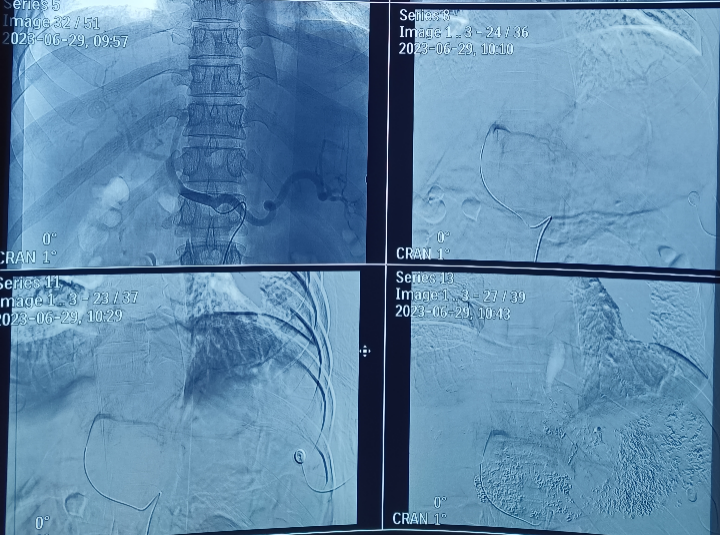

经过严密的病情分析和风险评估,诊断为:原发性肝癌 Ⅲb期,肝功能Child-Pugh  B级。目前暂时无法手术治疗,拟行经导管肝动脉灌注化疗栓塞术(TACE),但患者肝脏肿瘤瘤体巨大,周围血管受肿瘤压迫,迂曲明显,普通导管难以直达病灶,且患者BMI偏高,双侧股动脉触诊不明确,手术难度明显增加。放射科副主任医师张新异详细阅片,细致查体,并与患者及家属耐心解释沟通后,决定为患者行经导管肝动脉灌注化疗栓塞术(TACE)。6月29日,张新异在介入放射科为患者成功实施TACE手术,术中采用微导管通过迂曲的肝动脉,直达肿瘤,减少了对正常肝脏的副损伤,大大缩短了术后恢复的时间。手术过程顺利,术中及术后患者无明显不适,手术当天即可下床行走。

为什么要用到微导管精细介入  精准栓塞——微导管肝动脉灌注化疗栓塞术给肝癌患者带来希望!_https://www.jmylbn.com_新闻资讯_第2张术中影像

此次的肝癌介入治疗就是在不开刀暴露病灶的情况下,在腹股沟韧带下1-2cm处作为穿刺点,在影像设备的引导下,经股动脉穿刺处引入导丝导管,找到肿瘤的供血动脉,对病灶局部进行治疗,手术精准(在X光的指导下)、微创、无痛,全过程仅需局部麻醉,因此通常术后一天即可下床行走。